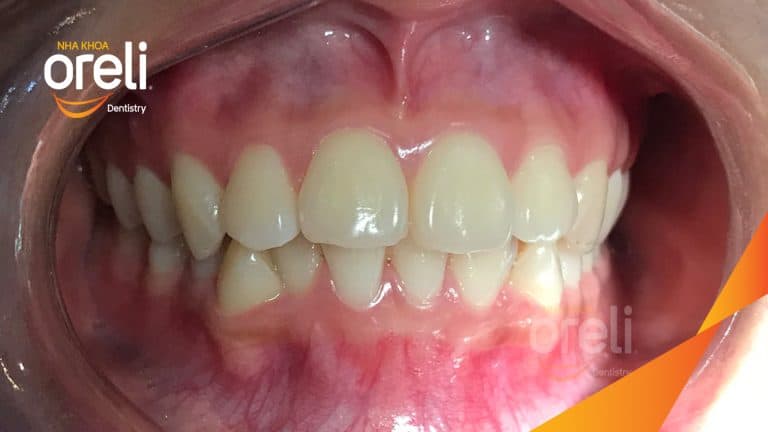

Ca niềng chỉnh chen chúc sai khớp cắn hạng 3 móm nhẹ – Kết quả thực tế ở Oreli Niềng răngChen chúcMóm Xem thêm